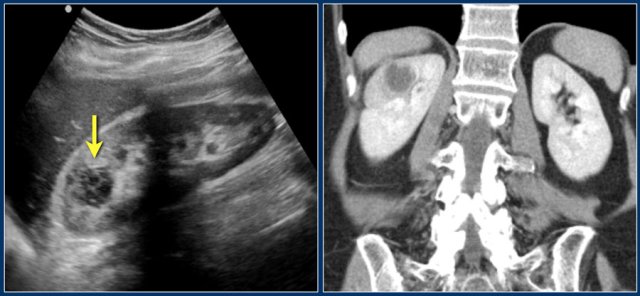

This patient had a typical presentation with right flank pain and laboratory findings consistent with a urinary tract infection.

The ultrasound image shows a hypoechogenic lesion with some echolucency, which indicates a fluid-containing component.

This proved to be an abscess.